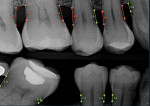

New technology and innovative approaches to care, such as incorporating AI technology into dental practice software, can improve the method and means of patient education, enhance clinical efficiency, improve provider standardization, facilitate clinical decision-making, and promote intra- and interprofessional collaboration.2 Some types of AI-powered radiograph analysis can measure from the cementoenamel junction (CEJ) to the crestal bone, which adds objective data to assist dentists in their clinical decision-making and diagnostic consistency.

The use of AI also can help improve patient engagement, which can facilitate optimal health outcomes and health service utilization.33 Further, improving health literacy via patient education enables patients to better understand their condition, which can lead to an improvement in health behaviors and self-care techniques, potentially reducing future treatment costs.2,38 Using AI technology, dental providers can empower patients by means of presenting unambiguous and visual health information. This empowerment can improve comprehension irrespective of underlying determinants and, ultimately, increase rates of treatment acceptance and utilization (Figure 1).